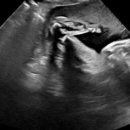

• 야탑로65번길 | 분당차병원 시험관 성공 후기 : 3년의 기다림 끝에 아기 천사를 만났습니다👶🏻

이식 후기⏫️ ​ 주치의는 이정은 교수님이셨고 감사하게도 전원 후 첫번째 시도만에 지금 나는 12주 3일차 건강한 아기 천사를 품고 있다🥹 ​ 26.1.30 (금) 12주 2일차가된 튼튼이 ​ 정말 길고 깜깜한 터널에서 드디어 빛이 보이는 입구를 찾았고 그 빛을 향해 터널을 빠져나가고 있는 기분이 드는 요즘,, ​ 6주차 초기에는...

중후기 임산부들에게 정말 필요한 서비스인 것 같아요. ​ ​ ​ 저는 임신기 근로시간 단축을 위해 최대한 빨리 진료를 본 건데요. 개인적으로 임신확인서가 필요한 게 아니라면 5주차 병원 진료는 굳이 안 가도 될 것 같았어요. 태아의 심장 소리가 들리는 7주에 첫 산과 진료를 봐도 무관할 것 같습니다. ​ ​ ​ ​ 분당차 산후...